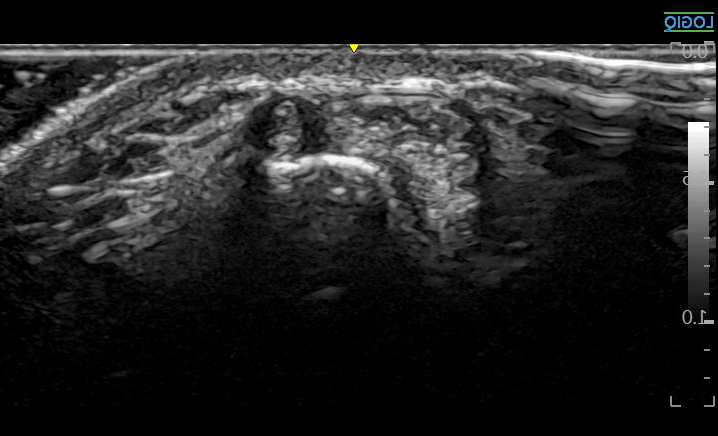

초음파 도침과 약침,

열결혈

이러한 드퀘르벵 건초염은

염증과 유착이 주요한 문제이기 때문에

유착을 제거하는'초음파 도침'부터먼저 시술합니다.

초음파 도침

건강한 힘줄은 건드리지 않고,

유착 부위만 도침으로 떼어내는 거죠.

초음파 약침

이어서 지대 주변 염증 부위에초음파 약침을 시술합니다.

이것이 바로 '한의 초음파'에서 표방하는

정밀 **'표적 치료'입니다.